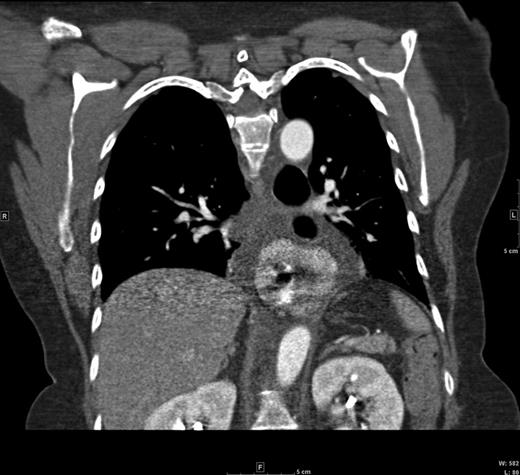

A 60-year-old female with a long-standing gastroesophageal reflux disease and known type III paraesophageal hernia presented to the emergency department with acute epigastric pain, dysphagia and vomiting. She noted a 1-month history of progressive dysphagia as well. Computed tomography (CT) revealed a large paraesophageal hernia with significant surrounding fluid concerning for incarceration (Figs 1 and 2). Owing to these findings and her discomfort, emergent laparoscopic repair of her paraesophageal hernia was recommended.

Coronal CT view of the paraesophageal hernia and mediastinal fluid.